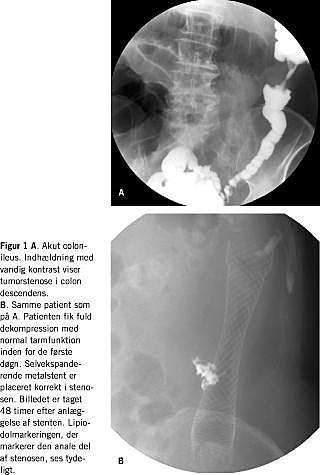

Selvekspanderende metalstent for colonileus

I alle tilfælde, hvor der er mistanke om colonileus, bør en oversigt over abdomen følges op med en vandig kontrastindhældning for at lokalisere stoppet. Selvekspanderende metalstent (SEMS) anvendes til ikkeoperativ behandling af malign kolorektal obstruktion og anvendes på to områder. Ved palliation af ikkekurabel sygdom, hvor symptomgivende obstruktion kan ophæves, hvorved kolostomi undgås, og god livskvalitet opnås i den resterende levetid (Tabel 1 ). Det andet område kaldes bridge-to-surgery , hvor obstruktionen ophæves, tarmfunktion normaliseres, almentilstanden forbedres, og præcis stadieinddeling kan udføres inden endelig stillingtagen til eventuelt elektivt behandlingstilbud. Såfremt kurativ behandling ikke kan gennemføres kan SEMS tjene som eneste behandling, evt. sammen med palliativ terapi (kemo- og/eller stråleterapi samt radiofrekvensbehandling (RF) af eventuelle levermetastaser). SEMS anlægges på to måder - enten ren ra-diologisk eller kombineret radiologisk/endoskopisk [2]. Ved ren radiologisk metode føres kateter og guidewire gennem obstruktionen under gennemlysning, og stenten anlægges derefter over wiren. Den kombinerede endoskopiske og radiologiske metode er den hyppigst anvendte. Et behandlingsendoskop (der er langt nok til sikkert at nå til obstruktionen) med minimum 3,7 mm's arbejdskanal føres til tumor. Der kan evt. tages biopsi af tumor til histologisk verifikation. Analt for tumor injiceres langtidsholdbart depot af røntgenkontrast i slimhinden. Tumorstenosen passeres med kateter og guidewire, og luminal vandig kontrast indgives oralt for obstruktionen. Dette sikrer korrekt passage af tumor og anvendes til udmåling af passende stentlængde. Stenten lægges dernæst over wire gennem arbejdskanalen og placeres således både under endoskopisk og radiologisk kontrol (Figur 1A og B ).